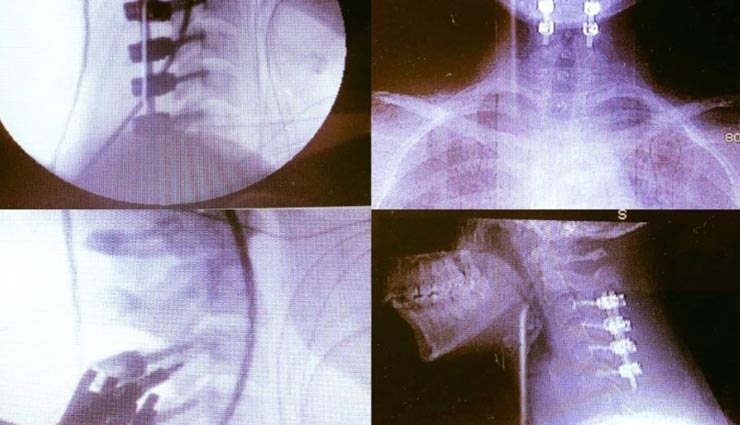

दरअसल, समथा स्मिथ (32) जब डॉक्टर के पास पहुंचकर अपने सिरदर्द और गर्दन दर्द के बारे में बताया तो डॉक्टर ने सारि चीजों को देखने के बाद बताया की उसको Ehlers Danlos syndrome नामक एक अजीब तरह की बीमारी से जूझ रही है जो कुछ ही महीने में उसकी मौत हो जाएगी।

यह सुनकर समथा स्मिथ हैरत में पड़ गयी। डॉक्टर ने बताया की इस बीमारी की वजह से स्मिथ के कनेक्टिव टिशु काफी कमजोर हो गए है। जिससे उसकी खोपड़ी उसकी रीड की हड्डी को तोड़ रही थी। डॉक्टर ने बताया की इस केस में खोपड़ी का दबाव इतना ज्यादा हो जाता है की अगर जल्द ऑपेरशन न किया जाये तो गर्दन टूटने का भी खतरा रहता है। जिससे समथा स्मिथ की जान भी जा सकती है।